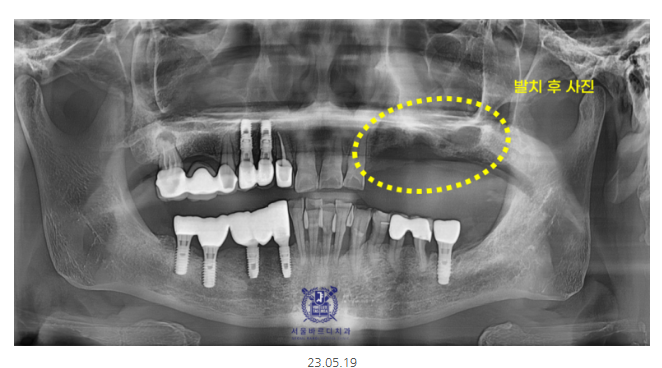

처음 내원 시 사진입니다.

전반적으로 풍치가 진행되셨네요~

왼쪽 위가 불편하신 게 가장 크다고 하셨는데요.

좀 특이한 모양이죠~?

맨 끝 치아가 머리만 둥둥 떠있네요.

예전에 많이 쓰이던 치료법으로

캔틸레버 브릿지라 불립니다.

한쪽만 지지된 채로 다른 끝은 공중에 떠있는 형태를 뜻해요.

이러다 보니 허공에 떠 있는 치아의 힘까지

앞쪽 치아가 받게 되어서

무리를 주게 됩니다.

오랜 시간 이런 힘이 축적이 되면

멀쩡했던 앞쪽 치아들까지 상하게 되는데요.

힘이 누적해서 가해져서

잇몸 속의 뼈와 치아의 뿌리도 계속해서 손상되게 되는데요.

그래서 사진을 보시면 앞쪽 치아 뿌리가 드러났죠~?

잇몸뼈가 내려가서 그런건데

바로 손상되었다는 증겁니다!!!

x-ray 상에서 까맣게 보이는 부분이

뼈가 녹은 부분입니다.

미사 임플란트 전 뼈이식만 했을 때의 사진입니다.

잇몸 뼈가 많이 녹은 상태라

발치를 하면서 뼈이식이 동시에 진행되었습니다.